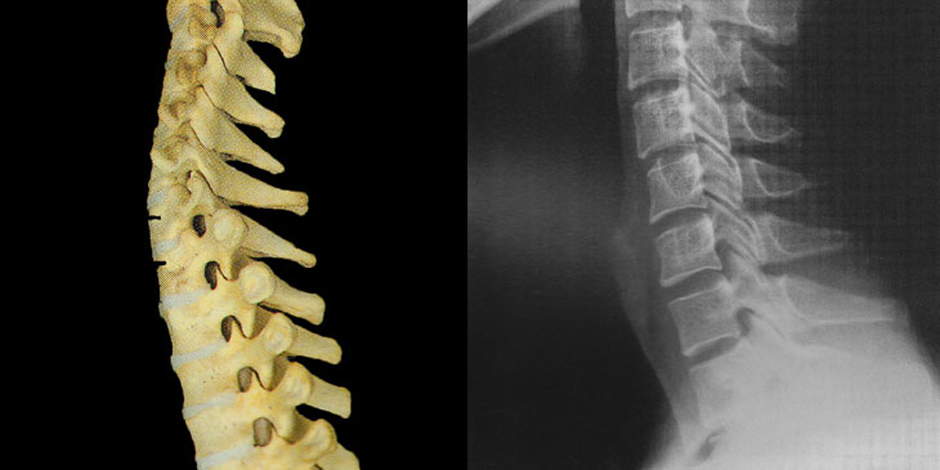

なぜ交通事故の追突でこのような様々な辛い症状が出てしまうのか?

人間の首はもともと後ろから外力が加わるということを想定しているつくりにはなっていません。首は真後ろからの外力(衝突)に対しての防御機構を持っていないのです。頚椎は後ろからの衝撃に弱い形態となっています。

靭帯や椎間板にも大きな外力に対抗出来る程の強度はありません。そして筋肉は収縮時であれば防御機構として役に立つのですが、なにゆえ追突事故は不意に訪れるので筋肉を収縮させる時間的な余裕がなく防御機構として機能しません。